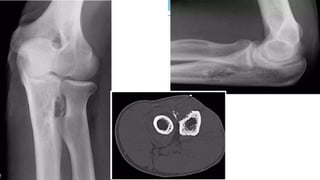

GCT O s t e o c l a s t o m a s

• Name coming from its histological picture

• • GCT containing richly vascular tissue with spindle cells and numerous giant cells

• • It neither forms bone nor cartilage

• • Locally aggressive

• • Can recur after excision

• • Age

• • 20-40 y e a r s

• • 3% develop in immature skeleton

• • L o c a t i o n

• •around the knee: distal femur and proximal tibia: 50-65%

• • distal radius: 10-15%

• • sacrum: 4-10%

• • vertebral body: 5-10%

• A lucent lesion typically situated beneath the articular surface

• E c c e n t r i c

• Narrow z o n e o f transition

• 'soap-bubble' pattern of calcification

• No sclerotic margin

• • overlying cortex is thinned, expanded or deficient

• • Soft-tissue mass may be present

• • No calcification or ossification until complicated by f r a c t u r e

• • CT Scan & MRI

• • To delineate soft tissue extension

• • B o n e s c a n

• • Increased activity in blood-pool phase

Plain film & CT features